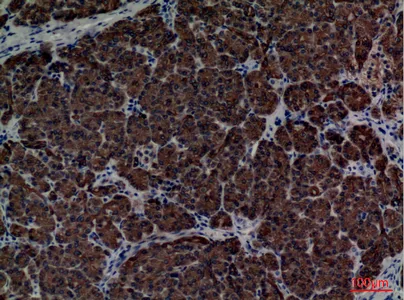

alpha 1 Fetoprotein Rabbit Polyclonal Antibody

Cat: APRab00486

Size1:50μl Price1:$150

Size2:100μl Price2:$280

Size3:500μl Price3:$1200

Size2:100μl Price2:$280

Size3:500μl Price3:$1200